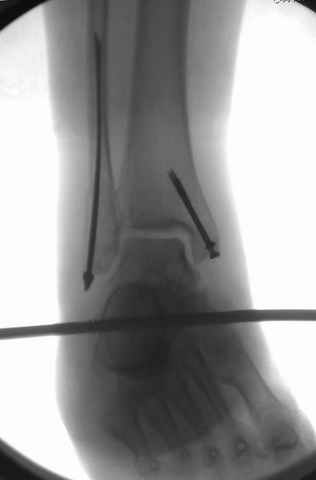

Второй случай сделан из одного разреза

Дж

ЕЧ LISS plate, mininvasive approach - luxurous !

На прямой проекции послеоперационного Рг макроскопически все выглядит очень анатомично, при микроскопическом ( :-)) ) рассмотрении можно все-таки заметить вальгизацию тарана, суставная щель в латеральном отделе сустава несколько уже , чем в медиальном при отсутствии латерального смещения тарана. У меня был аналогичный случай (без LISS , без мини доступа) с вальгусным наклоном тарана при восстановленном ankle mortise при последовательном наблюдении с интервалами в 6-8 недель в послеоперационном периоде отмечалось прогрессирующее сужение суставной щели в латеральном отделе сустава, закончившееся посттравматическим ОА, к счастью боли умеренные, купируемые аналгетиками или своими эндорфинами:-))(активная пациентка, у которой нет времени на болезни....) Какова жизненная ситуация в приведенном вами случае? И последнее, что я хотел бы прояснить для себя - фиксация внутренней лодыжки: я обычно комбинирую фиксацию компрессирующим винтом со спицей - по идее ротационная стабильность должна быть лучше, чем один винт, каковы ваши наблюдения в этом плане?